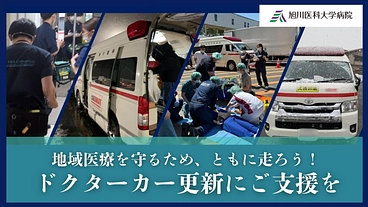

地域医療を守るため、ともに走ろう|ドクターカー更新プロジェクト

- 現在

- 8,455,000円

- 寄付者

- 277人

- 残り

- 27日